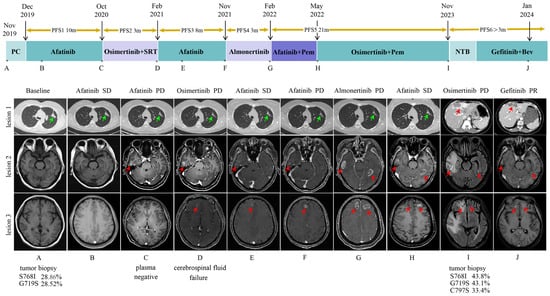

2. Case Presentation